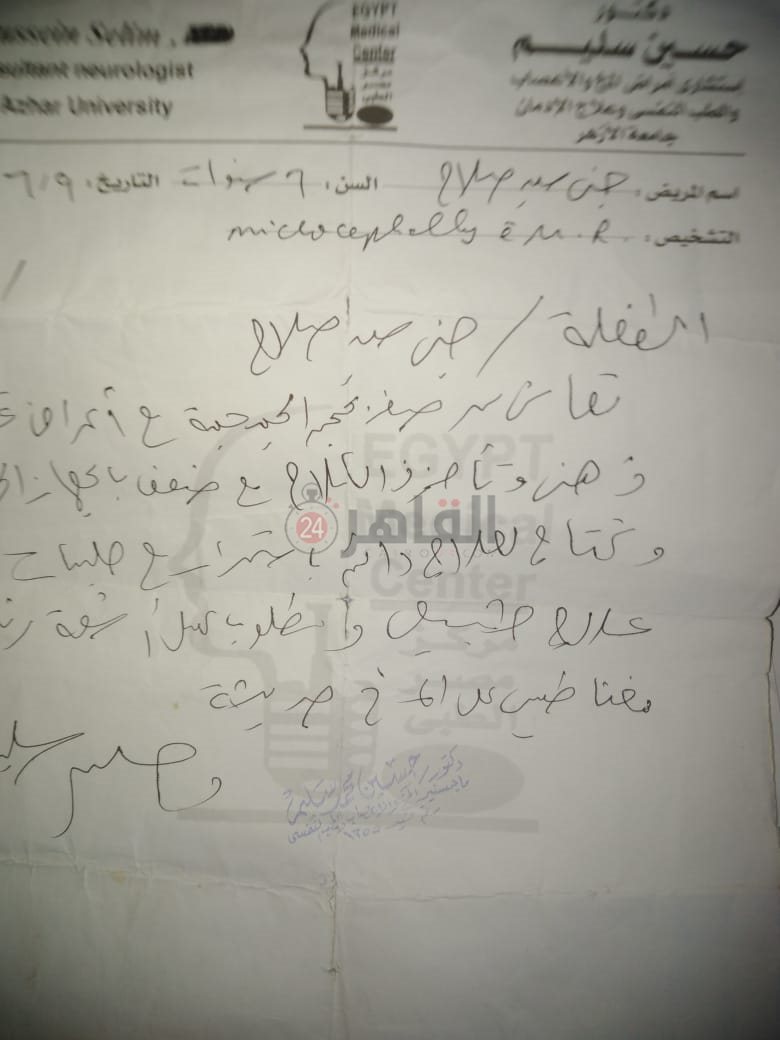

من جانبه، قال صلاح سيد، والد الطفلة جنى صلاح، إن ابنته تعاني من ضمور في المخ منذ ولادتها، نتيجة خطأ طبي، أدى إلى نقص كبير في الأكسجين لديها.

وأضاف في تصريحات خاصة لـ "القاهرة 24": "جنى تبلغ من العمر 6 سنوات، لا تستطيع المشي أو الوقوف على قدميها، نتيجة إصابتها بضمور في المخ منذ ولادتها".

وأوضح أن الطبيب الخاص بها أكد أن هناك داء خارج مصر يحسن من حالتها، ولكن باهظ الثمن، وتحتاج تناوله بشكل دوري.

واستكمل:" حاليًا تتناول أدوية شرب عادية، لحين توفيرالدولة علاجها من خارج مصر"، مشيرًا: "مفعتش قضية على الدكتور، ورضيت بقضاء ربنا".